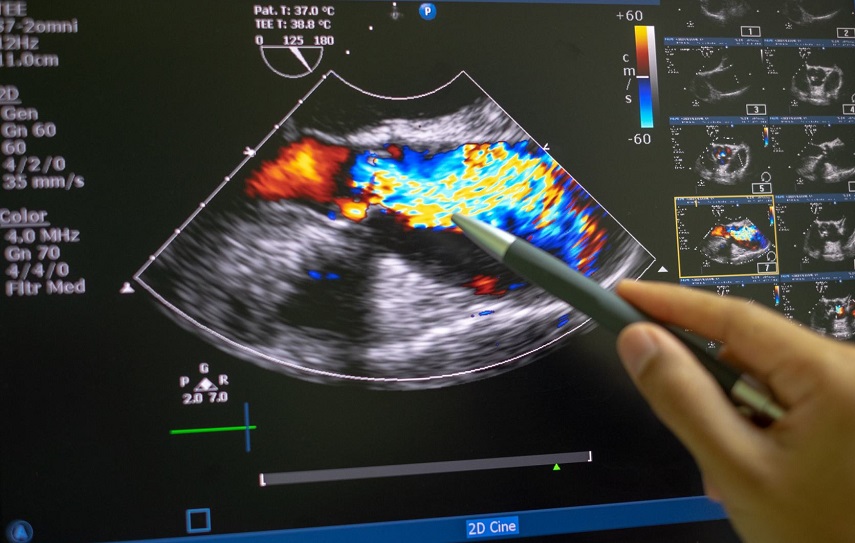

L’eco transesofageo (ETE) è una procedura diagnostica avanzata utilizzata in cardiologia per ottenere immagini dettagliate del cuore e dei grandi vasi. A differenza dell’ecocardiogramma tradizionale, l’ETE prevede l’inserimento di una sonda flessibile nell’esofago, che si trova a stretto contatto con il cuore. Questo approccio consente di superare le limitazioni dovute alla struttura toracica e di fornire immagini di qualità superiore.

- Immagini dettagliate – Gli ultrasuoni vengono utilizzati per creare immagini in tempo reale, fondamentali per individuare anomalie strutturali e funzionali del cuore.